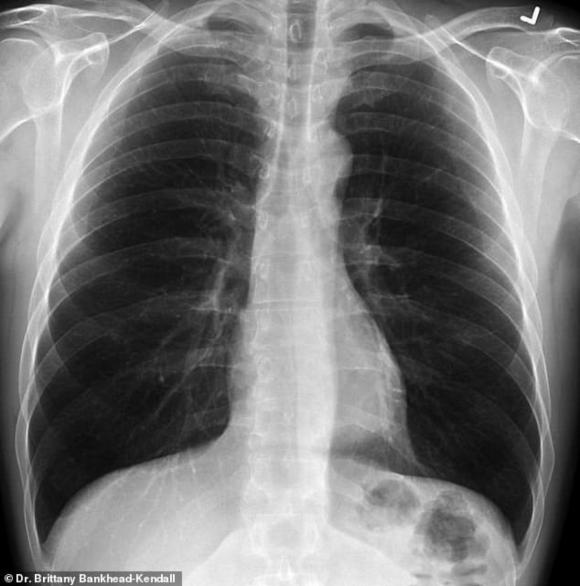

Phim của người khỏe mạnh có nhiều khoảng đen, cho thấy họ có thể hít vào đủ lượng oxy cần thiết. Phim chụp phổi người hút thuốc thì có nhiều khoảng mờ, còn của bệnh nhân Covid-19 thì gần như trắng xóa.

Phổi khỏe mạnh. Ảnh: Bác sĩ Kendall.

Những khoảng mờ trên phim chụp phổi thường là chỉ dấu của dịch lỏng, vi khuẩn, hoặc tổn thương và vết sẹo.